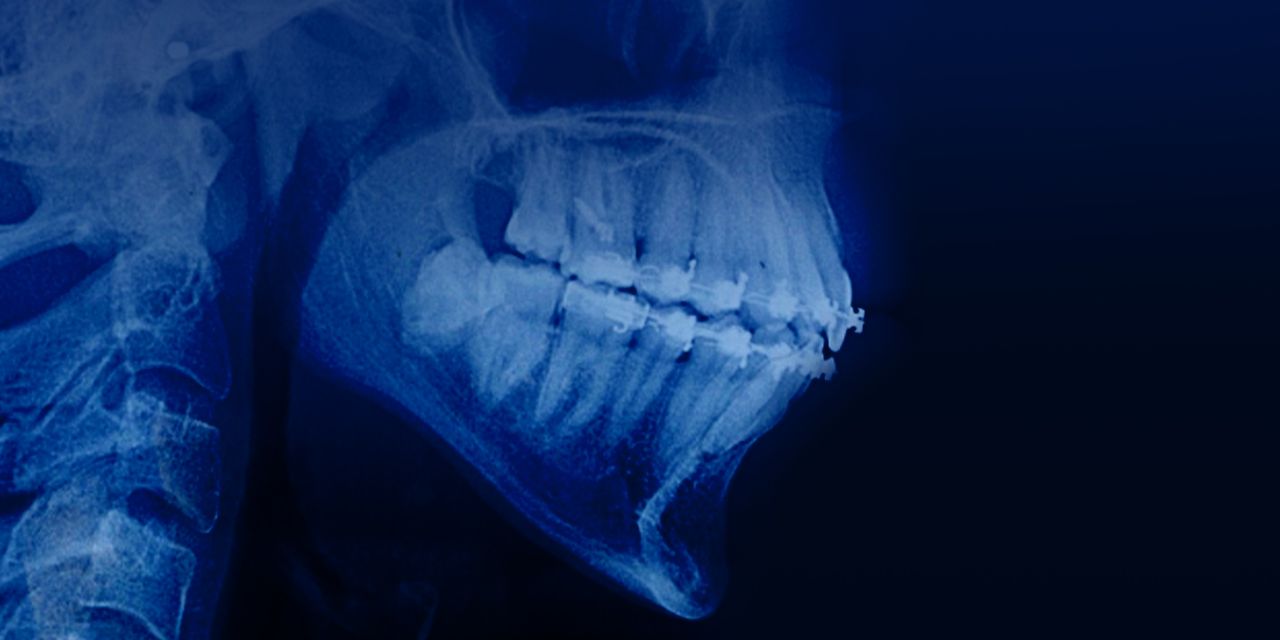

Orthodontic Treatment for Adults with Damon System

– Treatment of adult patients: the philosophy of the Damon system

– Non-surgical correction of class 2 and class 3 in adults

– Indications for the use of bone plates and mini screws